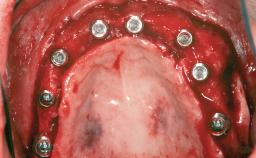

A 47-year-old Caucasian woman with a single-tooth edentulous space at the site of the left maxillary canine was referred for treatment. She had undergone traumatic extraction of this impacted canine several months before referral. Her chief complaint was the dissatisfying appearance of her smile. The patient desired a stable and esthetic rehabilitation of the site. Her dental history showed no evidence of periodontal disease or bruxism. She had no systemic diseases, was not taking any medications, and did not smoke. The extraoral examination revealed a high lip line and an inadequate soft-tissue volume at the defective canine site. Large black triangles were visible between the canine and its adjacent teeth.

Augmentation Materials Autogenous chips|Membrane

Soft Tissue Grafting Simultaneous